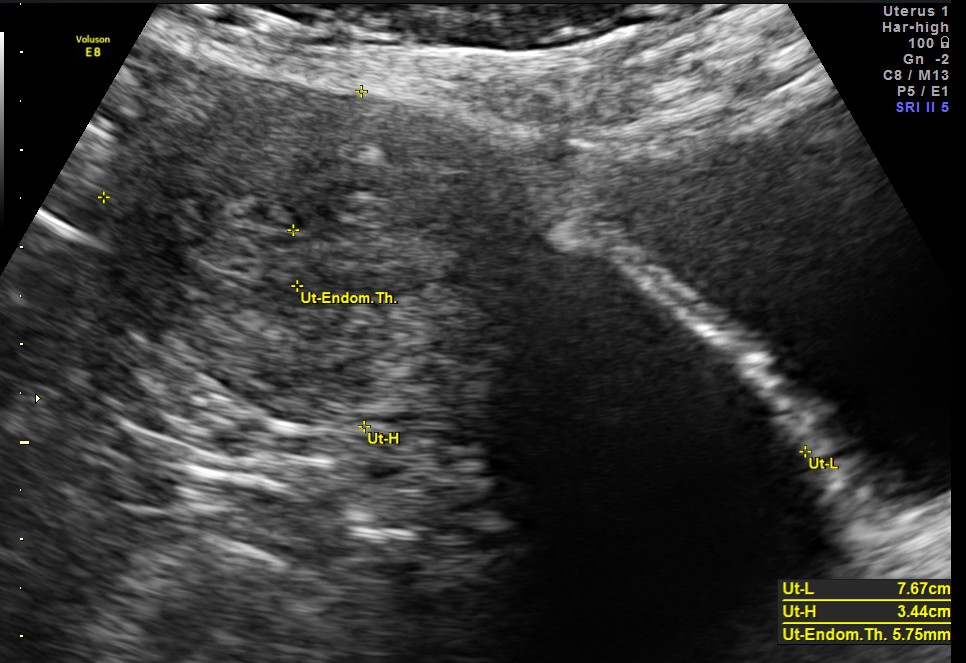

This was a 53 year old post menopausal lady who was evaluated for intermittent leucorrhoea. She had a carcinoma of breast and was operated earlier. She was on T.Tamoxifen for the past 3 years.The endometrial thickness was between 5.75 to 6.43 mms .Colour doppler showed increased vascularity.

It would be useful to remember that the endometrial thickness upto 8 mms can be considered as normal in post menopausal women on Tablet Tamoxifen.

In post menopausal breast cancer patients being treated with tamoxifen endometrial thickness was considered normal when less than 8 mm.